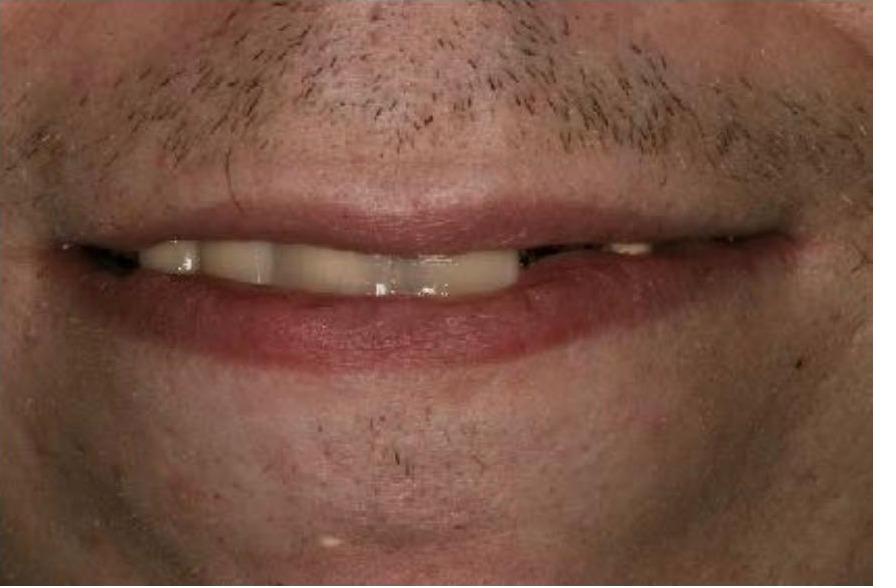

To improve this patient's dental health, esthetics and function, upper and lower implants were placed. I then fabricated an upper screw-retained implant bridge and a lower Overdenture, giving this patient back his smile and function. The patient was thrilled with the result and exclaimed "It looks good! I'll have all the women chasing me! I'd marry me if I wasn't already married!"

To improve this patient's dental health, esthetics and function, upper and lower implants were placed. I then fabricated an upper screw-retained implant bridge and a lower Overdenture, giving this patient back his smile and function. The patient was thrilled with the result and exclaimed "It looks good! I'll have all the women chasing me! I'd marry me if I wasn't already married!"